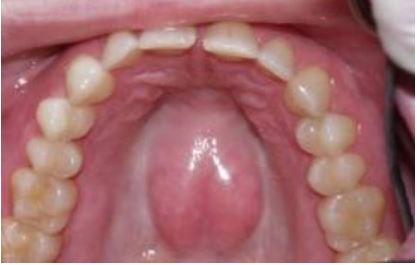

กรณีคนไข้ที่จำเป็นต้องถอนฟันจนหมด การพิจารณาใส่ฟันปลอมทั้งปาก อาจจะต้องมีการ เตรียมช่องปากด้วยการ ตัดแต่ง กระดูกที่แหลมคม หรือกระดูกนูนในบางตำแหน่ง เพื่อให้ ฟันปลอมทั้งปาก มีพื้นที่ในการยึดติดกับเหงือก

ลักษณะปุ่มกระดูกกลางเพดาน ที่จำเป็นต้องตัดแต่งก่อนใส่ฟันปลอมทั้งปาก